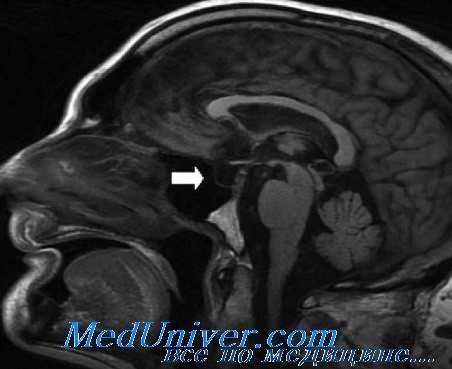

- МРТ области турецкого седла с контрастированием;

![МРТ гипофиза]()

При БИК в 80-85% случаев выявляют микроаденому гипофиза (опухоль до 10 мм), у остальных 15-20% — макроаденому (доброкачественное новообразование от 10 мм). [7]